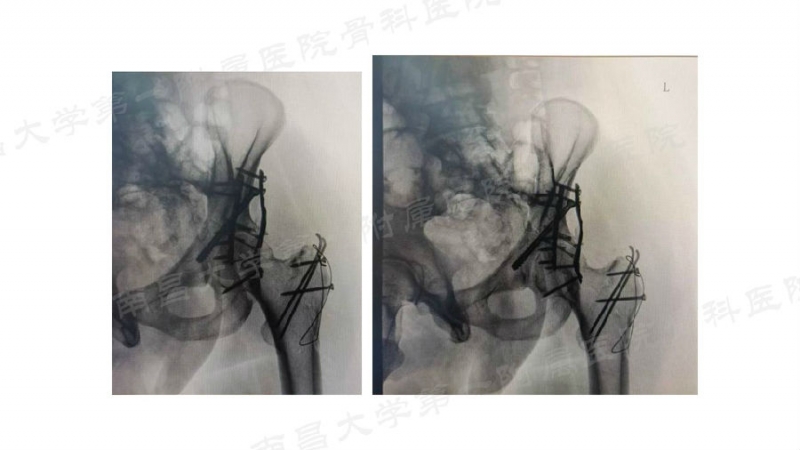

病例一

病例二

病例三